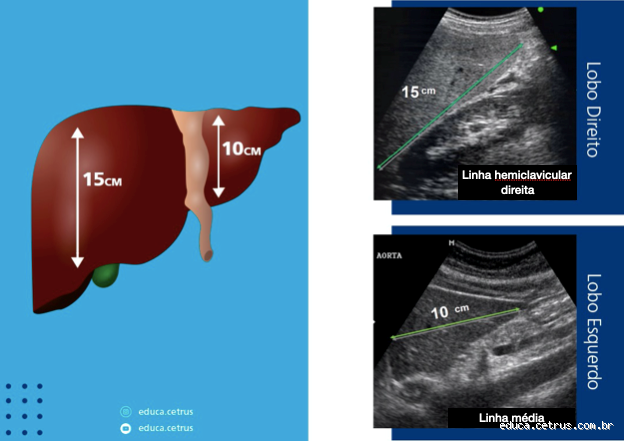

1. Ultrassom abdominal

Este é um dos exames mais comuns e acessíveis para verificar a saúde do fígado. O ultrassom pode mostrar o tamanho, a forma e a textura do fígado, além de identificar possíveis cistos ou tumores. Quando fui ao médico, ele pediu um ultrassom abdominal, e foi um exame tranquilo, sem dor, e deu para ver como o fígado estava bem no geral.